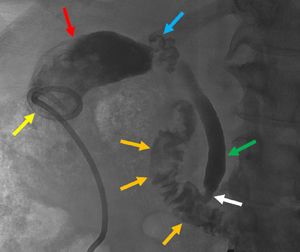

우상 복부 사분원 초음파 검사는 담낭염을 진단하는 데 가장 일반적으로 사용된다.[4][26][27] 급성 담낭염을 시사하는 초음파 소견에는 담석, 담낭 주위 액체(담낭 주변의 액체), 담낭벽 비후(벽 두께 3mm 이상),[28] 담관 확장 및 초음파 머피 징후가 있다.[13]초음파 검사에서 담낭염의 특징적인 소견은 초음파 머피 징후(초음파 프로브로 담낭 압박에 의한 통증), 담낭벽 비후(>4mm), 담낭 종대(장축경>8cm, 단축경>4cm), 멈춘 담낭 결석, 데브리 에코, 담낭 주위 액체 저류, 담낭벽 sonolucent layer, 불규칙한 다층 구조를 나타내는 저에코대, 도플러 신호이다.

CT 스캔은 천공이나 괴사와 같은 합병증이 의심되는 경우에 사용될수 있다.[14] CT에서 담낭염의 특징적인 소견은 담낭벽 비후, 담낭 주위 액체 저류, 담낭 종대, 담낭 주위 지방 조직 내 선상 고흡수역 등이다.

MRI에서는 담낭 결석, pericholecystic high signal, 담낭 종대, 담낭벽 비후 등을 확인할 수 있다.

민감도가 더 높은 간 이미노디아세트산 (HIDA) 스캔은 초음파 검사가 진단적이지 않은 경우 사용할 수 있다.[13][14]